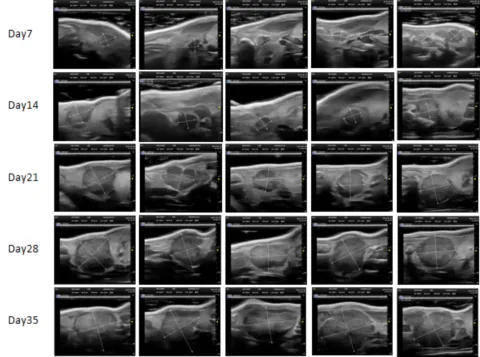

PDX Model (Growth Curve)

部分beats365PDX原位模型展示